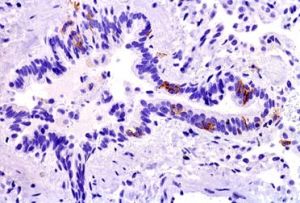

②郎格罕細胞(langerhanˊscell)大多位於棘層中上層、胞漿透明。細胞來源於骨髓,具有吞噬細胞功能,具有攝取、加工並遞呈抗原作用。細胞表面具有HLA-DR抗原,IgG的FC段受體及Ia抗原等。近年來用OKT6或Leu6及免疫螢光或免疫細胞化學技術是觀察此種細胞最好的方法。是與免疫有關的一種細胞。在電鏡檢查核呈腦回狀有切跡。胞漿內有一特徵性的網球拍樣顆粒(Bibeck顆粒)亦稱郎格罕顆粒。